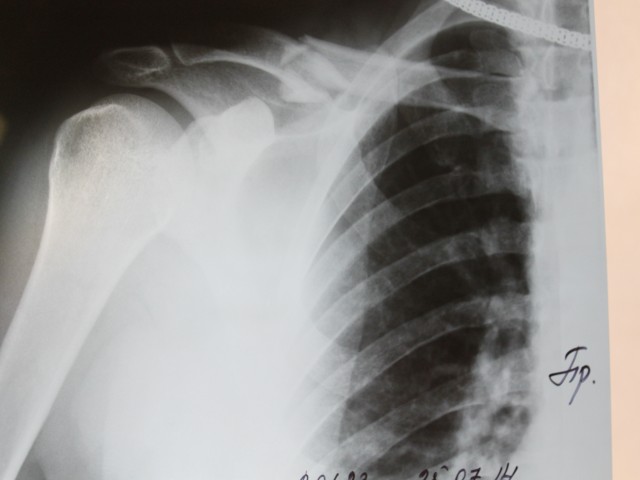

Шлем\каска да и защита конечностей не спасает вот от этого!!!

Главное здравый моСК и техника!!!

Вложения

(54.21 Кб) Просмотров: 8173

1408177695617.jpg

1408177695617.jpg (12.21 Кб) Просмотров: 8173

ты расскажи как ты так умудрился?

СообщениеGT_икс » 10.09.2014, 21:30

Все просто, обидно и смешно!!! 3 года катаюсь (катался) по горам Краснодарского края, падал, вставал и ехал дальше.... А обидное то ,что "убрался" в городе на тротуарной плитке, точнее на микро кочке в 150 метрах от дома ((((...... Скорая помощь приехала быстро и отдельное спасибо

Андрею Пыченкову он был дежурным именно на этом вызове!! Андрей тоже зареган на форуме, но я не помню его ник..... Андрей отзовись!!!!